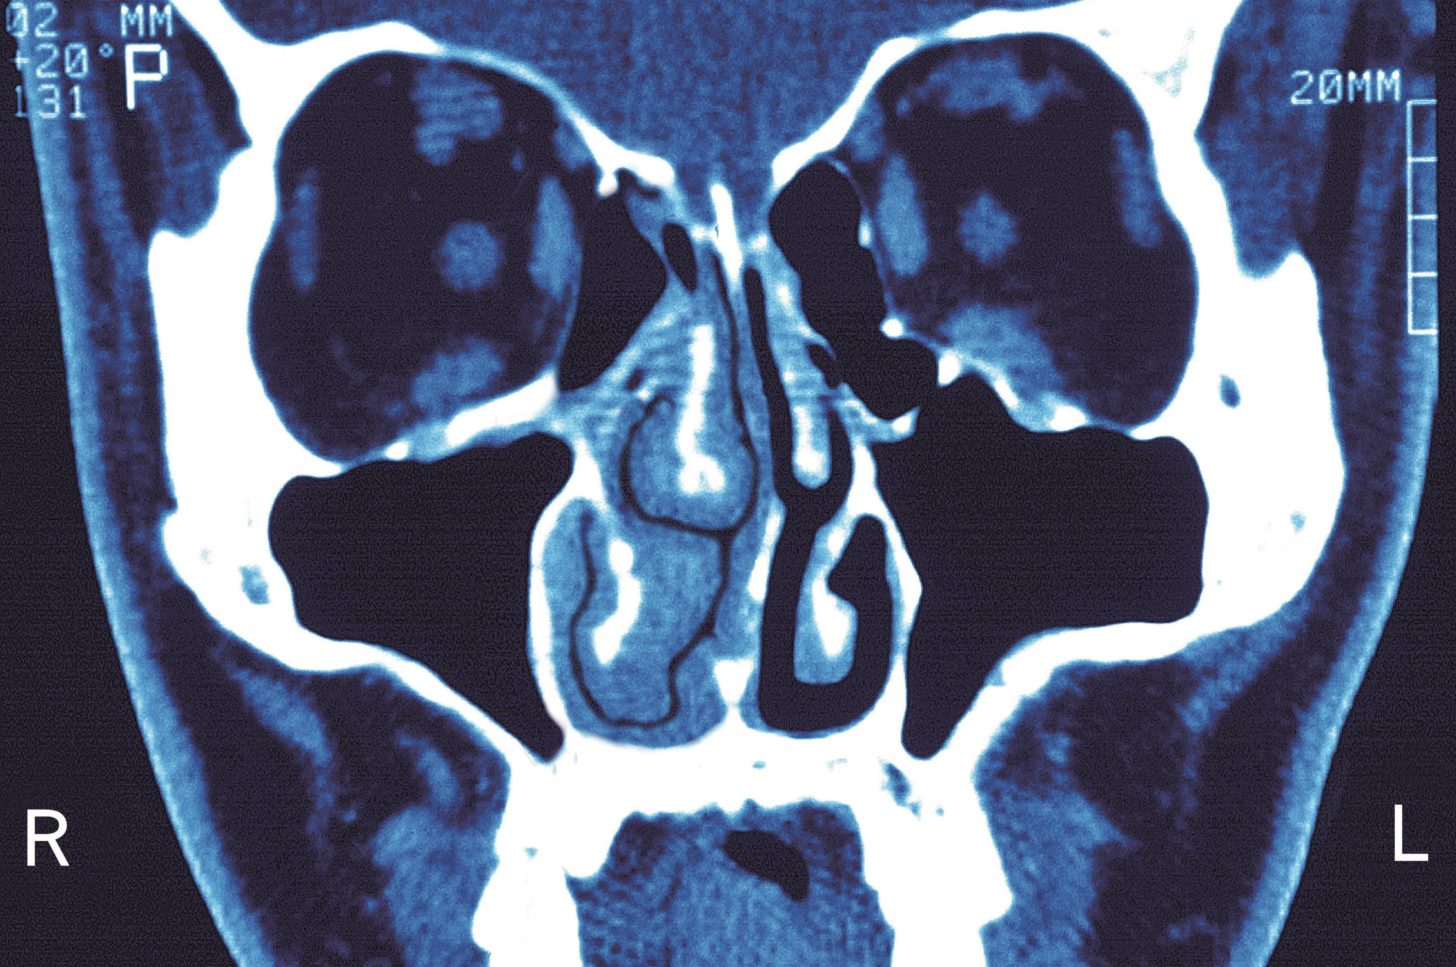

From medizzy.com

Treatment of sinusitis MEDizzy Sinusitis Treatment Steroids A possible bacterial infection might need to be treated with. Oral corticosteroids like prednisone may be prescribed for sinusitis to help alleviate symptoms like pain, pressure, and congestion. Nasonex (mometasone) rhinocort (budesonide) steroid nasal sprays, drops, or oral corticosteroids may also be used if you have nasal polyps that. Antibiotics are sometimes needed to treat sinusitis caused by bacteria. Intranasal. Sinusitis Treatment Steroids.